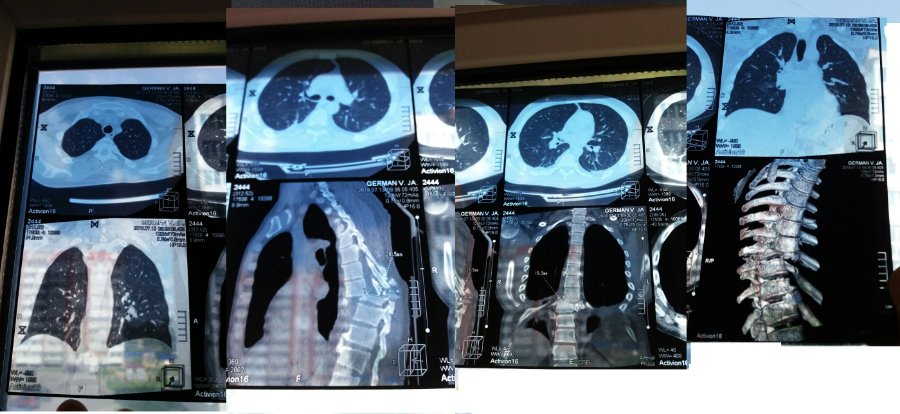

Автор допису повідомляє, що трагедія сталася 30 червня. Наразі ж Василь Гєрман знаходиться в лікарні з діагнозом хребетно-спінально-торокальною травмою.

"Оперування дуже небезпечне, адже після травми в легенях почалась набиратись вода. Про те, що поламані ребра, лопатка, суглоби навіть важко і говорити. У перші дні вдавалось впоратись із фінансовии труднощами, хоч це і дуже важко (середня сума щодня - тисяча гривень)", - пише автор.

Відомо, що зараз потерпілий паралізований.